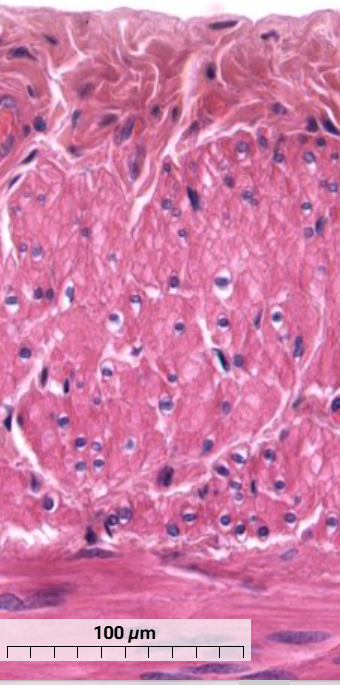

What muscle cell is this and how can you tell? (Longitudinal section)

Skeletal muscle cells

Can see sarcomere striations from thick and thin filaments

Satellite cell nuclei of mostly heterochromatin can be seen on the surface of muscle cells